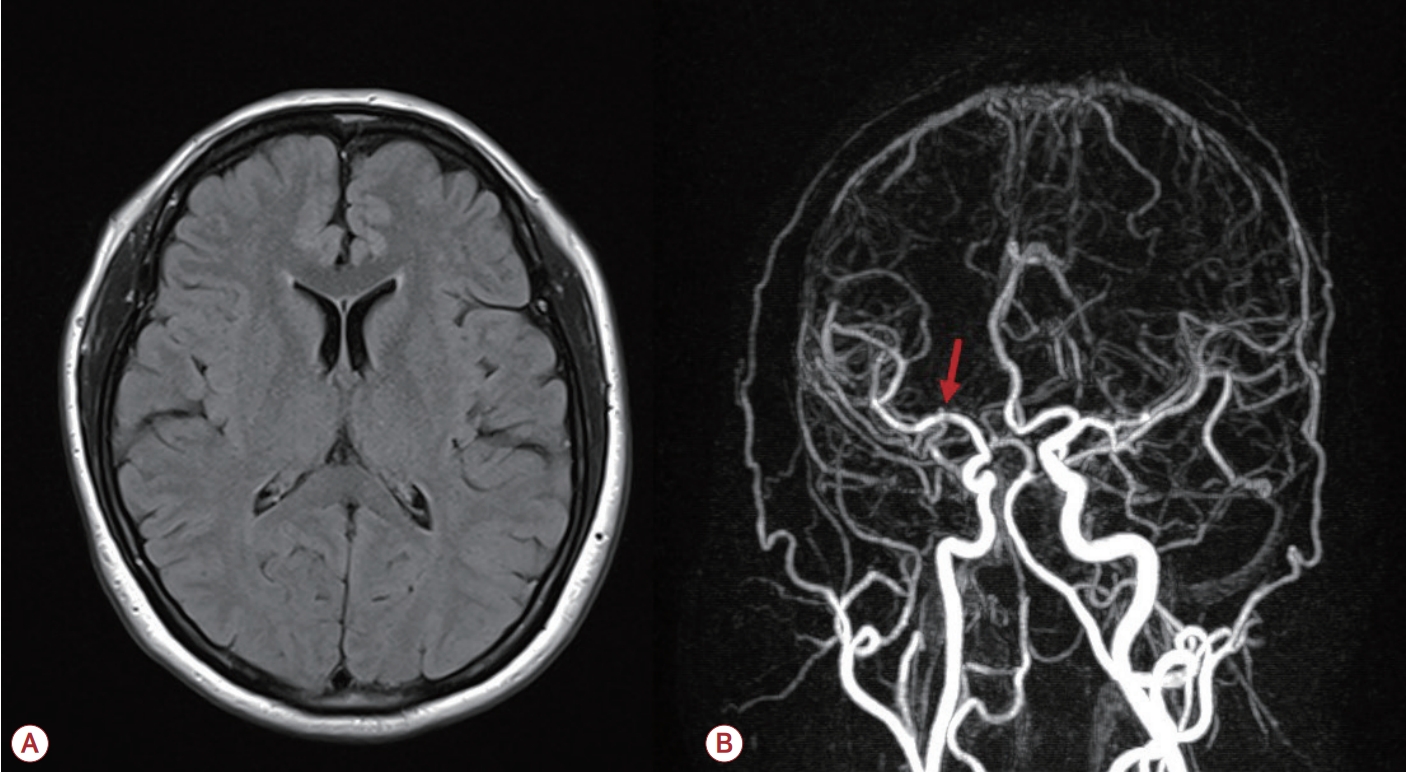

환자는 뇌졸중을 배제하기 위하여 magnetic resonance imaging (MRI)을 시행하였으며 확산강조영상(diffusion-weighted image, DWI) 및 액체감쇠역전회복(fluid attenuated inversion recovery, FLAIR) 영상에서 급성 병변과 허혈성 병변이 관찰되지 않았다. 또한 뇌 자기공명혈관조영(magnetic resonance angiography, MRA) 결과 오른쪽 중대뇌동맥(middle cerebral artery, MCA)의 경미한 국소 협착 이외에는 뚜렷한 이상 소견이 발견되지 않았다(Fig.). 신경전도 검사 결과 손목굴증후군(carpal tunnel syndrome, CTS) 외에 없었으며 바늘근전도 검사에서 근육병 소견은 확인되지 않았다. 또한 뇌파 검사 및 반복신경자극 검사에서도 정상 범위 내 결과를 보였다.

Figure.

Brain magnetic resonance imaging (MRI) and magnetic resonance angiography (MRA). (A) Brain MRI reveals minimal leukoaraiosis in the bilateral cerebral white matter. (B) Brain MRA shows mild focal stenosis in the right middle cerebral artery, indicated by the red arrow.